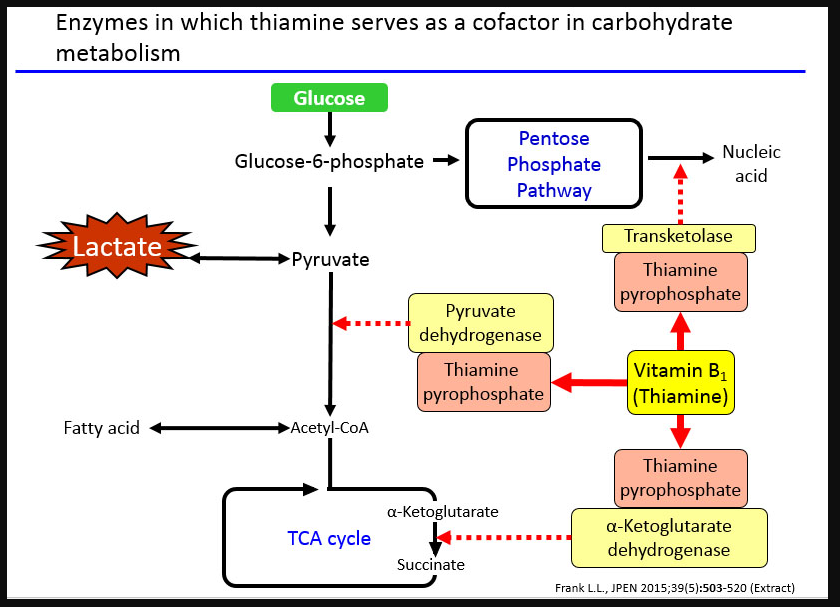

Many researchers believe that the entire brain is involved with memory, in some way or another (Lashley, 1950). However, some key areas have been identified (shown below in Figure 1.) and include the amygdala, hippocampus, cerebellum, the prefrontal cortex and the synapses linking them all (Mayford, Siegelbaum, & Kandel, 2012).

Forming memories involves various steps and stages (Atkinson & Shiffrin, 1968). To begin with the brain receives sensory information from several sources in different formats, such as smell, taste, sound, vision and touch. At this point the information that has the individuals focus will be rehearsed in the STM store and ‘encoded’ (transformed into a format the brain can retain). Following this, the information is then ‘committed to memory’ and stored in the LTM, readily available to be retrieved when needed. The information not rehearsed or not regularly retrieved will eventually be forgotten. Figure 2. Below illustrates this process.

Amnesia is essentially the instances where memory, or the process of forming memories, fails. The processes of forming, maintaining and recalling memories is extremely complex and as mentioned above involves numerous brain structures, if not the brain in its entirety. This can lead to numerous points of failure and thus numerous reasons for memory to fail; leading to amnesia.

However, as research has developed, and the mapping of the brain and its functions has developed researchers are becoming able to pinpoint the structure’s role within memory, such as the amygdala facilitating the encoding of memories to a more significant degree when the event is emotionally arousing (Josselyn, 2010). This means that when an individual suddenly fails to respond to stimuli that normally would have induced a fear response; a neurologist can narrow down their investigation and begin imaging of the amygdala with the expectation of some sort of abnormality (e.g. a lesion or tumour) affecting it’s functioning.